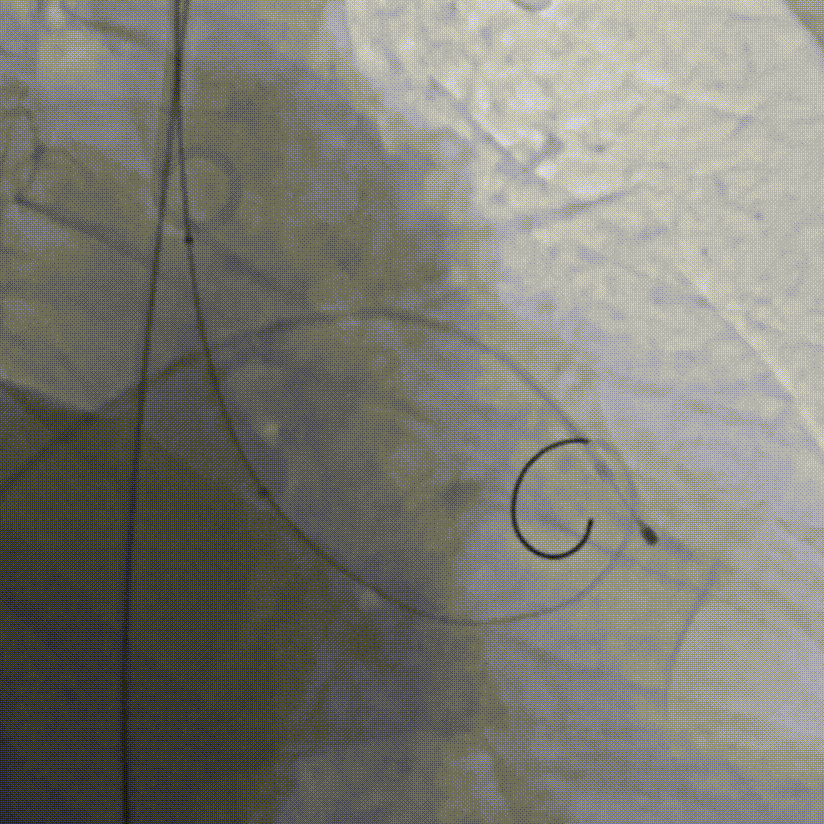

手术当日,在多学科团队的紧密监控与配合下,首先由心脏重症监护科蓝新平主任团队顺利建立VA-ECMO(图C),为患者筑起了坚实的“生命之桥”。随后,钟炜教授手术团队在影像学的精准引导下,凭借娴熟技术及团队默契配合,通过血管路径将人工瓣膜输送至心脏预定位置,一次精准释放,即刻解除了“心门”的梗阻(图D--G)。整个手术过程中,ECMO运行平稳,患者生命体征始终保持稳定,未出现预期中的血流动力学剧烈波动及消化道出血加重的情况,顺利完成手术操作。

D.成功跨瓣后行球囊扩张